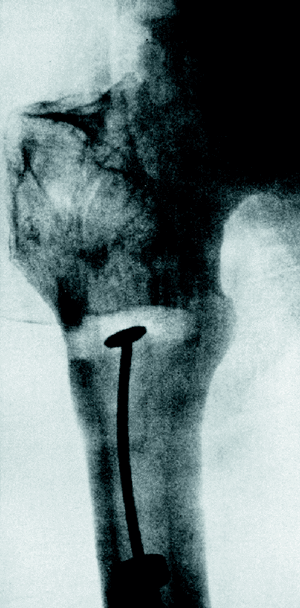

No tardó en percatarse de que el clavo era inestable en las fracturas proximales de fémur y en su afán de disponer un clavo adecuado para cada tipo de fractura, desarrolló un clavo cónico, para el tratamiento de fracturas pertrocantéreas y subtrocantéreas (Fig. 7) que, en 1940, cambió por un clavo bifurcado con una hendidura en la porción diafisaria que denominó en «Y» (Fig. 8), rudimento de lo que mucho más tarde sería el clavo gamma.

Figura 7. Radiografía de un clavo intramedular cónico.

Figura 8. Clavo intramedular en «Y».